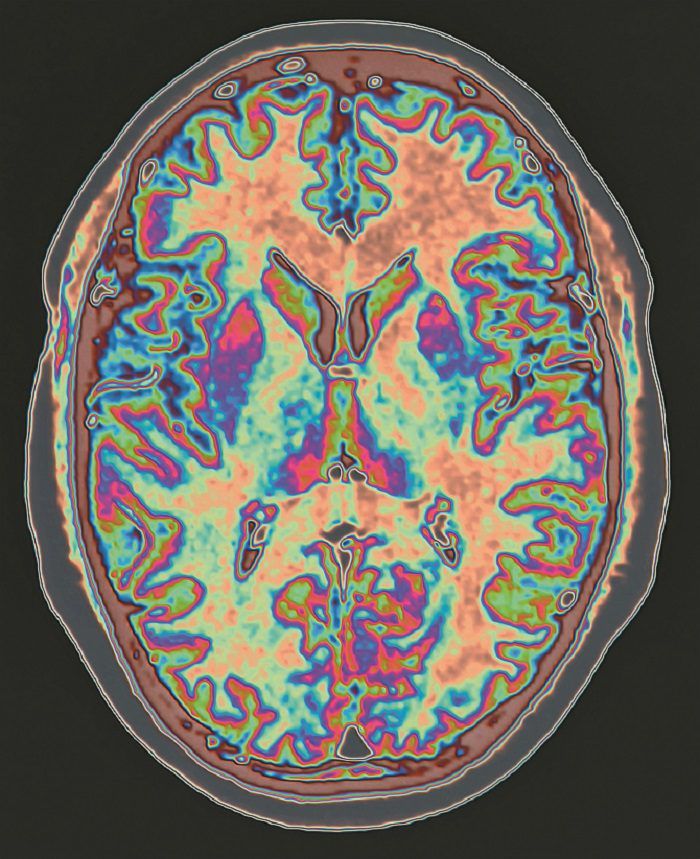

A 2015 study found that when people took an active placebo their depression symptoms decreased. PET scans showed increased brain activity in areas associated with emotion and stress regulation. This activity corresponded with an improved response to the future use of antidepressants.